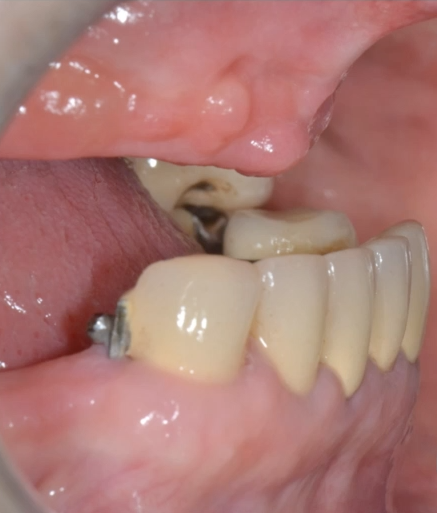

Pterygoid implants are an old therapeutic option for the

treatment of atrophic posterior maxilla that is often overlooked in today’s

treatment options. This lecture addresses the perceived anatomical risk that is

often associated with this procedure and tries to elucidate the controversies

on the subject. It will expose the scientific documentation of the procedure

and will present the modern approach in using the pterygoid implant for the

rehabilitation of totally and partially edentulous patients. The place of

guided surgery in performing this procedure is also discussed.